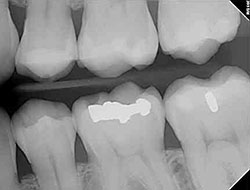

Digital X-Rays

Using the most advanced dental technology possible is just as important as staying up-to-date on the latest treatment techniques. Because our practice is dedicated to providing your child with the safest and most convenient treatment options available, we utilize advanced digital X-ray technology in our office.

Is a digital X-ray really safer?

Because we care about your child's entire body's health and well-being, we believe that reducing the amount of radiation exposure is extremely important. Although the amount of radiation used in dental X-rays is very small, the effect is cumulative, so all radiation counts. Digital X-rays can reduce your child's exposure to radiation by up to 80%!

What are the advantages of digital X-rays?

- We want your little one to be as comfortable as possible during their appointment, and digital X-rays eliminate the need to bite down on a sharp piece of film encased in plastic.

- There is no need to wait for the X-ray film to be developed before it can be viewed, so the entire checkup can be a lot shorter.

- The digital images can be enlarged and manipulated, giving the doctor a clear, more detailed look at your child's teeth.

- Because your child can see the image enlarged on a screen, they can better understand why taking care of their teeth is important.

- It's better for the earth! There is no need to use harmful chemicals to process film.

Our practice is focused on making your child's dental experience as comfortable as possible. At their next appointment, we'll be happy to answer any questions you may have.